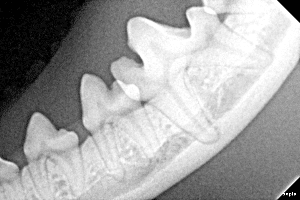

RTG stomatologiczne psów i kotów – Gdańsk

W SoskenVet 24h wykonujemy wewnątrzustne RTG stomatologiczne, które pozwala na dokładną ocenę korzeni zębów, zmian okołowierzchołkowych oraz struktur niewidocznych podczas badania klinicznego. Badanie RTG jest kluczowe w planowaniu skutecznego i bezpiecznego leczenia.

Tak. RTG stomatologiczne pozwala ocenić korzenie zębów i zmiany niewidoczne podczas badania klinicznego. Jest kluczowe w planowaniu ekstrakcji oraz leczenia kanałowego.